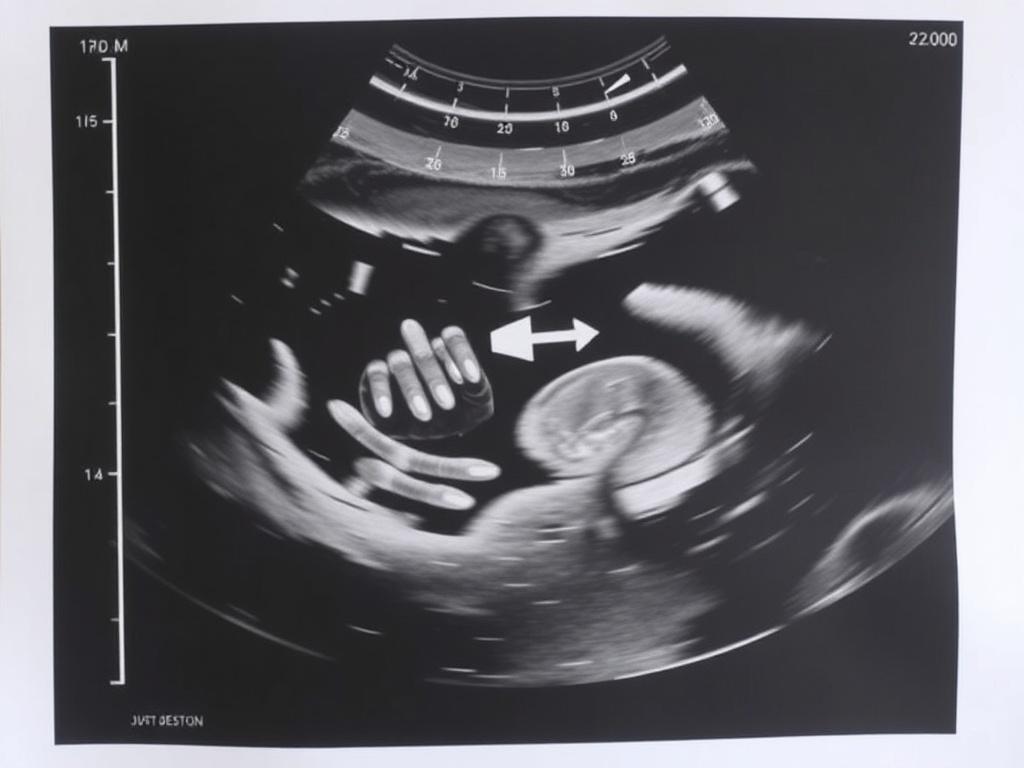

En ecografías obstétricas, las medidas son esenciales para estimar la edad gestacional y el crecimiento. Si recibes números, puede ser útil preguntar qué significan para ti.

- ¿Qué medidas han tomado y qué representan?

- ¿Cómo determinan la edad gestacional a partir de estas medidas?

- ¿La medida está dentro del rango normal para la edad gestacional estimada?

- Si hay alguna variación, ¿qué seguimiento recomiendan?

- ¿Con qué margen de error trabajan en esta etapa?

Entender las medidas te permite interpretar si lo detectado es una variación normal o si requiere vigilancia. Pregunta por el rango de referencia y qué pasos seguirán si algo no está dentro de esos límites.